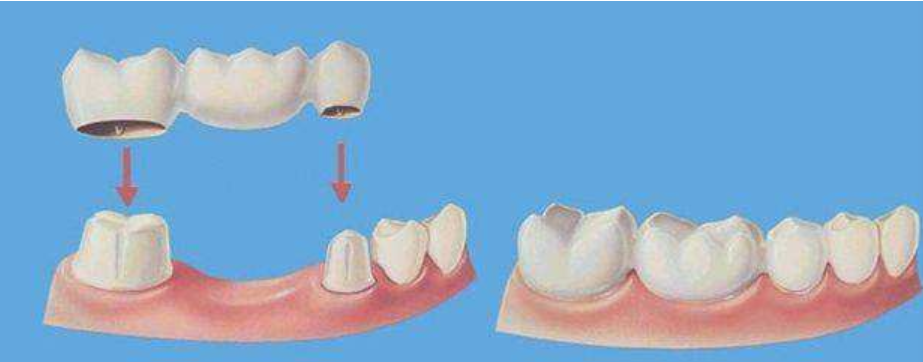

其次是固定义齿也被称为“烤瓷牙”、“镶牙”,烤瓷牙修复需要磨除两侧邻牙来将烤瓷牙固定,固定义齿装一颗牙的价格主要看义齿材料而定。

优点在于: 咀嚼能力较强;舒适、不影响舌头活动;美观,使用寿命较长。

而缺点在于:要求周边牙齿必须健康,须对周边牙齿进行磨平;不方便清洁,在烤瓷牙周边缝隙中容易残留食物渣。